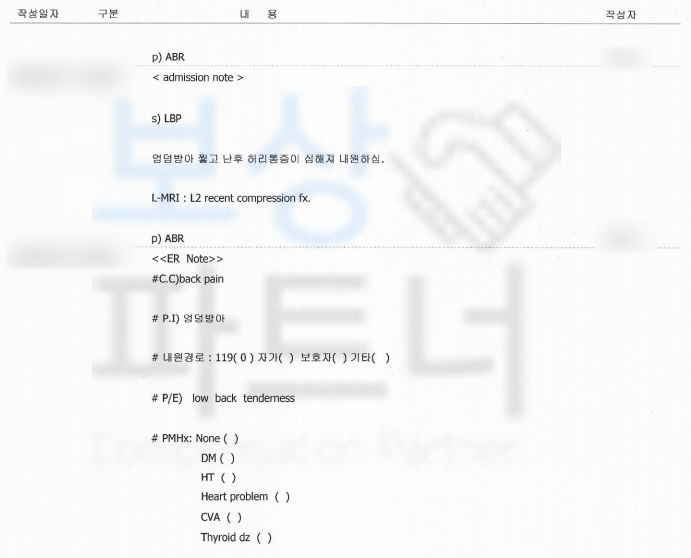

버스 운전업을 하시는 이@@님은 길을 지나가시다 많이 왔던 눈에 미끄러져 엉덩방아를 찧으셨는데요 “별일 없겠지” 하고는 허리가 아프셨지만 집에 들어가 하루 정도 쉬어야겠다고 생각하셨습니다.

하지만,, 다음날에도 극심한 통증에 바로 구급차로 병원에 내원하게 되었고

요추2번 압박골절 S32030

진단을 받으셨죠. 당시 시술이나 수술할 정도는 아니라

주치의는 8주간 허리보조기를 착용하며

안정을 취하자고 하였습니다.